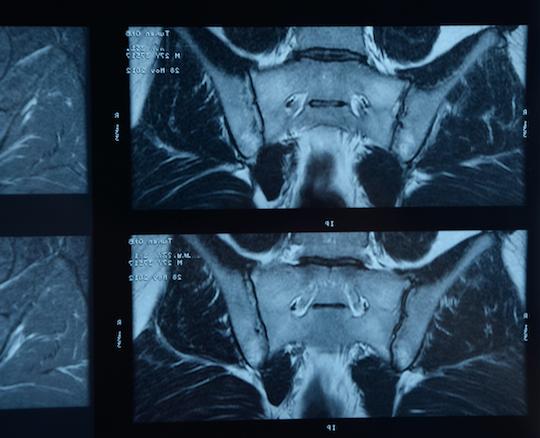

L'âge moyen des malades recrutés est de 37,9(11,0) ans avec une durée de la maladie de 3,7(6,2) ans et 51,2% sont des hommes. Une lésion radiographique des articulations sacro-iliaques, une sacro-iliite en IRM et un HLA-B27 positif ont été observés chez 46,9%, 81,9% et 75,0% des patients respectivement. L'ASDAS moyen à l'inclusion était de 3,0 (± 0,7) et l'ASAS-HI moyenne de 8,6 (± 3,7). Soixante-douze malades par groupe ont participé à la visite d'un an.